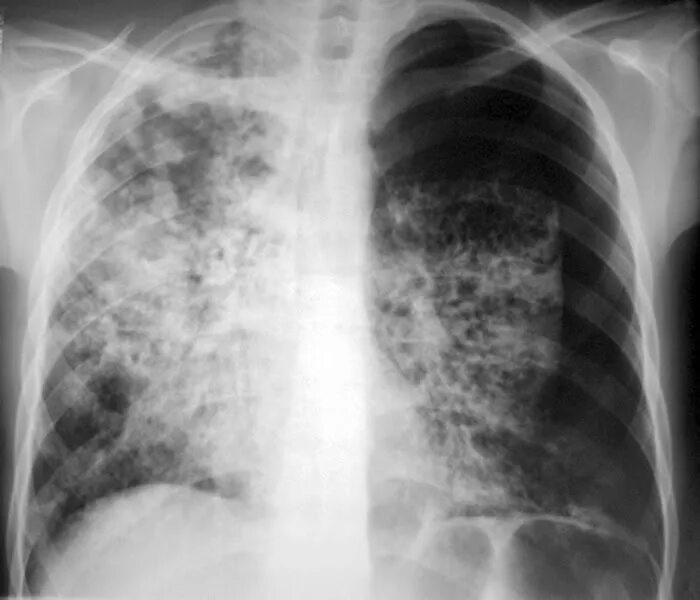

Поражение легких при туберкулезе